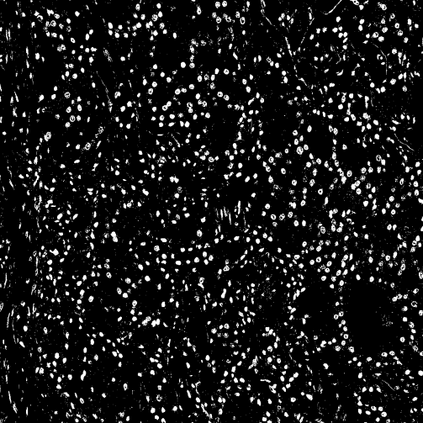

Pathologists diagnose and grade prostate cancer by examining tissue from needle biopsies on glass slides. The cancer's severity and risk of metastasis are determined by the Gleason grade, a score based on the organization and morphology of prostate cancer glands. For diagnostic work-up, pathologists first locate glands in the whole biopsy core, and -- if they detect cancer -- they assign a Gleason grade. This time-consuming process is subject to errors and significant inter-observer variability, despite strict diagnostic criteria. This paper proposes an automated workflow that follows pathologists' \textit{modus operandi}, isolating and classifying multi-scale patches of individual glands in whole slide images (WSI) of biopsy tissues using distinct steps: (1) two fully convolutional networks segment epithelium versus stroma and gland boundaries, respectively; (2) a classifier network separates benign from cancer glands at high magnification; and (3) an additional classifier predicts the grade of each cancer gland at low magnification. Altogether, this process provides a gland-specific approach for prostate cancer grading that we compare against other machine-learning-based grading methods.